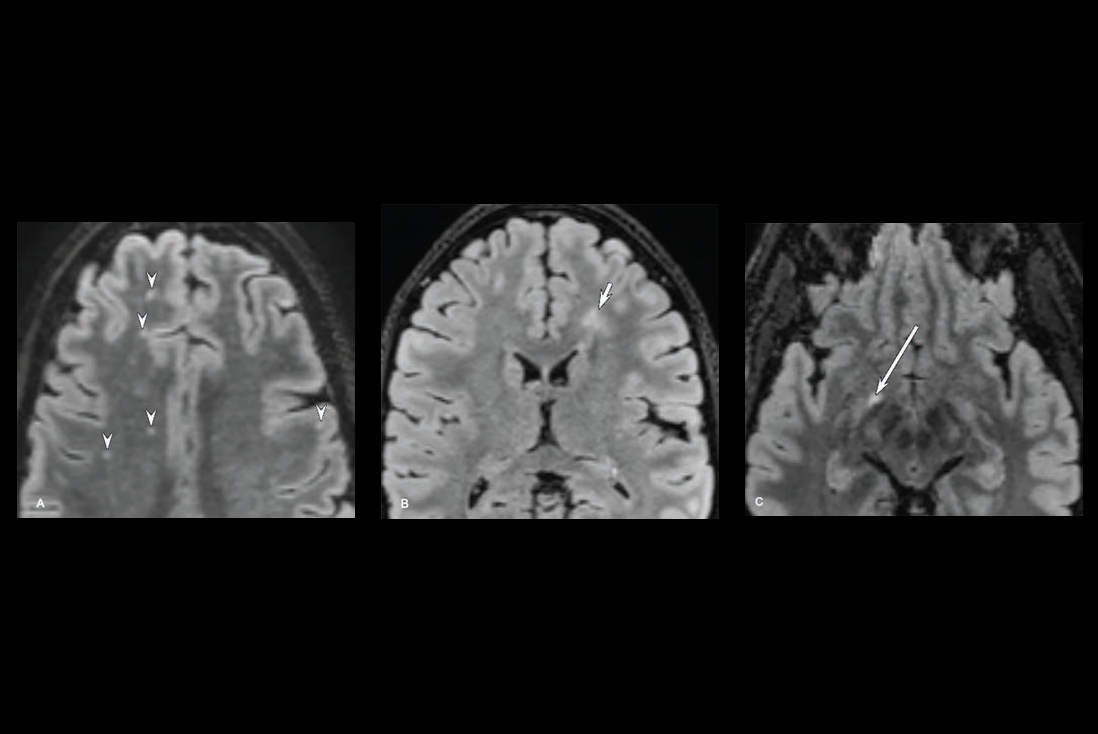

- Compared with the waiting-list control group, all participants with mTBI had decreased fractional anisotropy in the right cerebral peduncle, anterior limb of the internal capsule, posterior corona radiata, and cingulum-hippocampus at six- to 12-month follow-up. "Fractional anisotropy is a key measure of brain atrophy derived from diffusion-tensor imaging (DTI) and is widely used to assess axonal injury," the team noted.

- Greater improvements in the fractional anisotropy of the right posterior corona radiata after acupuncture were linked with persistent therapeutic effects of acupuncture at six- to 12-month follow-up.

Axial (top) and sagittal (bottom) diffusion-tensor imaging scans and bar graphs show fractional anisotropy (FA) values of white matter fibers after verum acupuncture. * = p < 0.001, Bonferroni-corrected for multiple comparisons. Error bars represent SDs. R = right hemisphere.RSNA